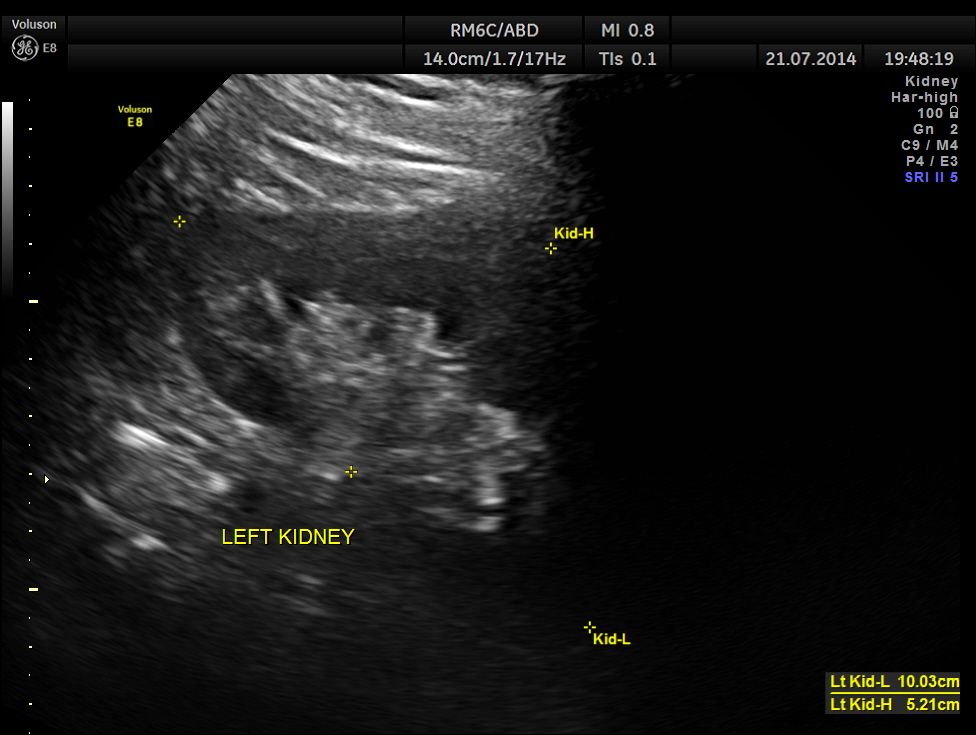

This was a 42-year-old gentleman , a known case of Insulin dependant Diabetes Mellitus. He was being evaluated by his physician for loss of weight and abdominal pain of a few months duration.

His abdominal ultrasound pictures are given below.